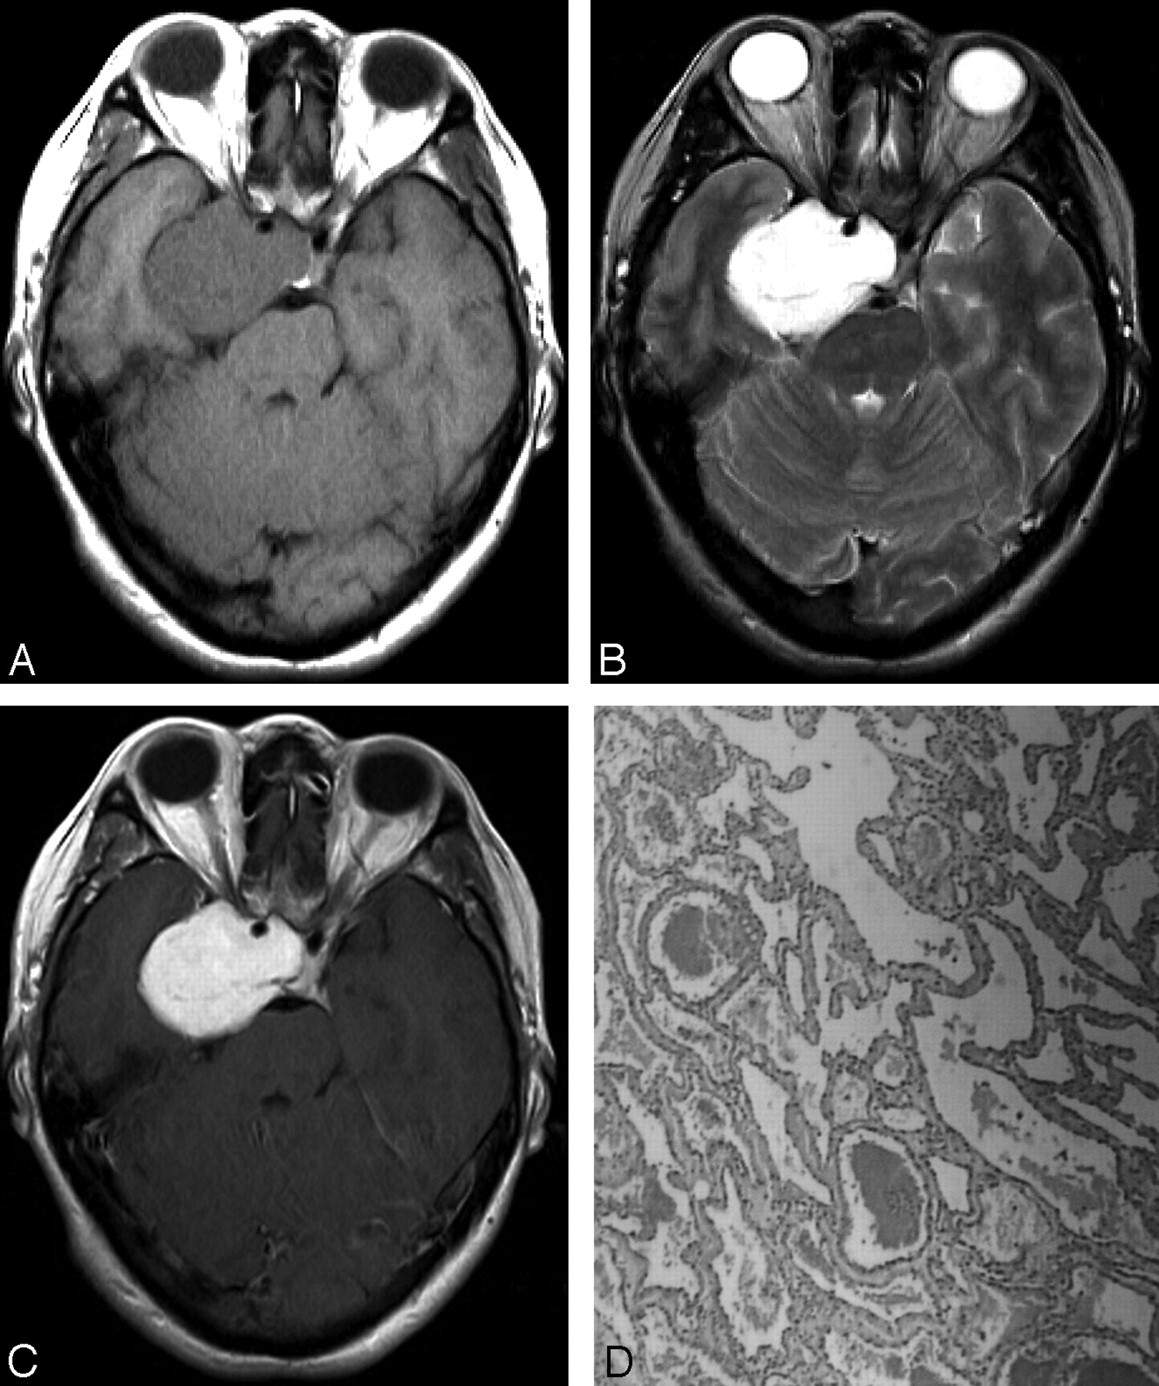

The respiratory membranes (bronchioles, alveolar ducts, & alveoli) are made up of eosinophilic hyaline, fibrin, & cell debris with necrotic type pneumocytes

Neonatal respiratory distress syndrome/ hyaline membrane disease

Neonatal respiratory distress syndrome/hyaline membrane disease

Has ground glass opacities

Ground glass opacities = Neonatal respiratory distress syndrome/hyaline membrane disease

Eonsinophilic Hyaline Membranes line the alveolar ducts and alveoli, made up of fibrin admixed with cell debris (necrotic type II pneumocytes) 🡪 Increased pulmonary vascular permeability, plasma leaks into the alveoli, which makes hyaline stain pink.

: Neonatal Respiratory Distress Syndrome / Hyaline Membrane Disease

: Neonate is presented with nasal flaring and grunting. This is due to surfactant deficiency, therefore need cortisol secretion (need to hit baby and starts crying, release of cortisol increased 🡪 Type II pneumocytes are responsible for secreting surfactant

Neonatal Respiratory Distress Syndrome / Hyaline Membrane Disease